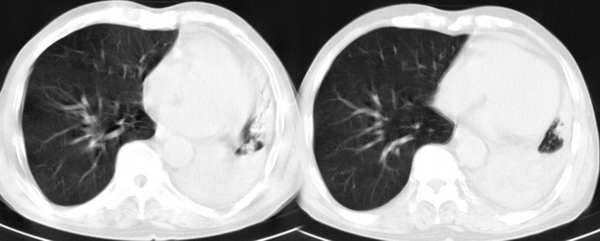

m67y外院ct诊断肺ca,现来我科复查ct

左肺下叶支气管狭窄局部见肿块影左肺下叶不张,肺癌应该没问题吧

典型中央型肺ca

左主支气管变窄,左下叶部分不张,考虑肺癌可能性大

考虑左下肺中央型肺癌并肺不张,建议支气管镜检查。

左下肺中央型肺癌并不张可能性大,为慎重起见,请楼主提供病史,以排除支气管内膜结核引起肺不张。

左中央型肺癌并左下叶肺不张,建议纤支镜检查.

左下肺中央肺ca并下肺不张